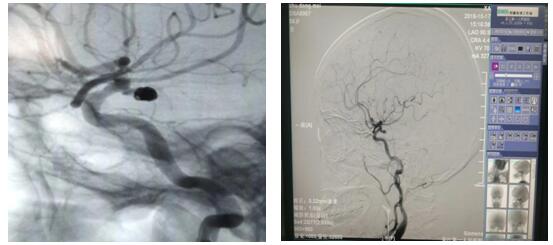

近日,56岁的朱女士因“左侧面部麻木2天”入院,完善颅脑磁共振及头颈部CTA检查,示左侧颈内动脉与大脑中动脉交界处动脉瘤。DSA检查后,明确诊断“动脉瘤、动静脉畸形”瘤体大小为4-5mm,患者存在病灶侧动眼神经麻痹,考虑瘤体压迫所致,经苏大附二院肖国栋主任会诊后在全麻下行DSA脑动脉瘤栓塞术,整个手术过程顺利,全程用时1.5小时,患者麻醉苏醒后安返病房,经护理人员精心护理,目前患者病情平稳,在积极康复中。颅内动脉瘤介入栓塞术在我院是首次开展,手术的成功完成标志着我院神经内科脑血管介入治疗又登上了一个新台阶。同时,也填补了我院在这一领域的空白。